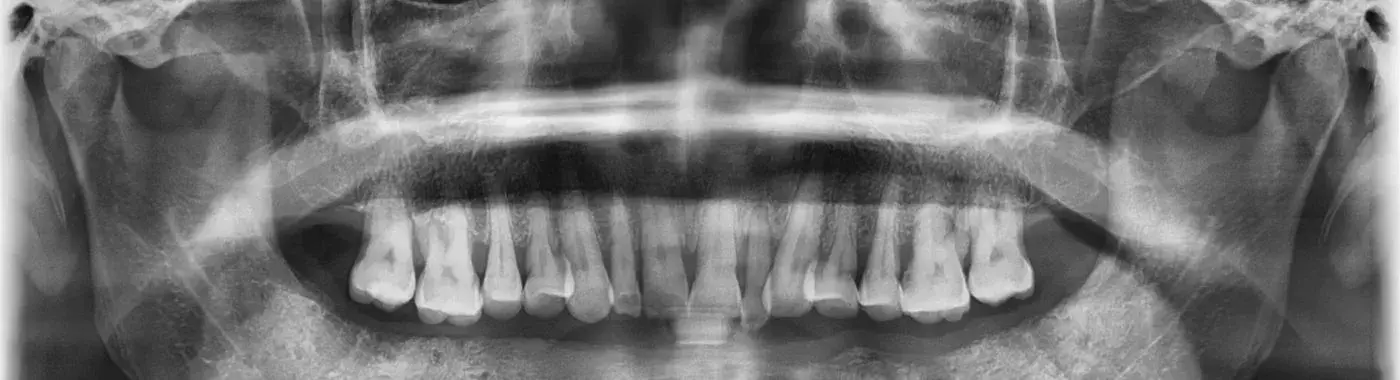

Osteoradionecrosis is defined as the necrosis (death) of bone tissue that occurs as a result of radiation therapy. This condition primarily affects the mandible (lower jaw) and maxilla (upper jaw) in patients who have received radiation for cancers in the head and neck region. The radiation can impair the blood supply to the bone, leading to tissue death, pain, and potential infection. ORN is a significant concern because it can severely impact a patient's quality of life, necessitating complex treatment strategies.

• Imaging Studies: X-rays, CT scans, or MRIs can help visualize bone changes and assess the extent of necrosis.